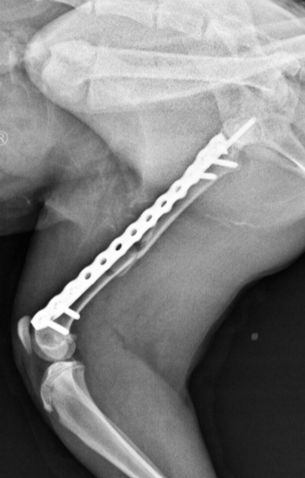

Botbreuken herstellen met platen van Synthes en kyon .

Specialisatie Patella luxatie ( losse knie)  kruisband herstel bij hond en correctieve osteotomies , kunstgroeve, kunstknie bij hond en kat .